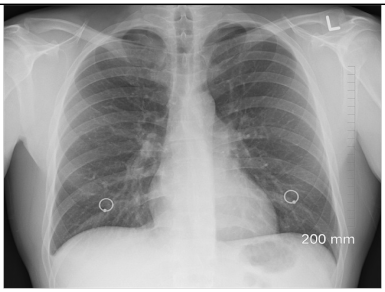

2.6.1. Test Procedure

The stress test involved simulating varying numbers of concurrent users querying the system. For each LLM, we executed 20 clinically relevant prompts, as shown in (Table A2) in the Appendix A. For each VLM, 10 different images with 2 prompts per image resulting in a total of 20 prompts per model were tested. The specific prompts used are listed in (Table A3) in the Appendix A. We tested user loads of 10, 20, 30, 40, 50, 75, 100, 125, and 150 users. In order to measure the robustness of the container as well as the robustness of JAVIS, this experiment queried the JAVIS back-end to measure the complete roundtrip response times. This approach ensured that the test accurately reflected real-world usage scenarios, including the overhead of back-end processing and model orchestration.